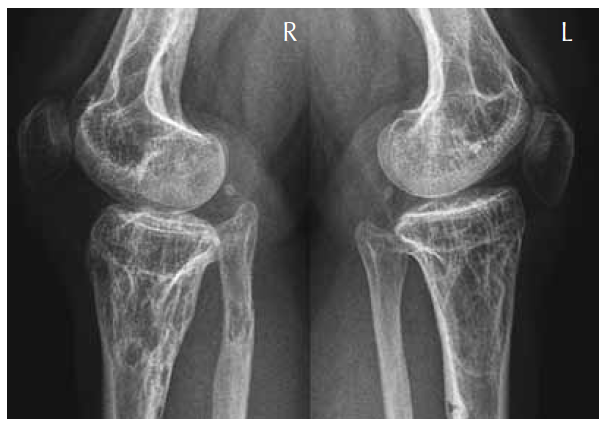

Lateral radiograph of the inferior femora and the super tibiae showed abundant calcification intermixed with areas of osteolytic lesions. Note multiple lucent lesions with bony islands and linear sclerotic changes, which extend from the epiphyses to involve the shafts (Fig. 2).

Fig. 2. Lateral radiograph of the inferior femora and the super tibiae showed abundant calcification intermixed with areas of osteolytic lesions. Note multiple lucent lesions with bony islands and linear sclerotic changes, which extend from the epiphyses to involve the shafts